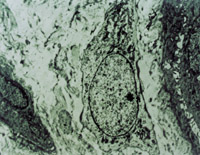

經(jīng)MEBT/MEBO治療5天,可見(jiàn)創(chuàng)面纖維細(xì)胞,成纖維細(xì)胞生長(zhǎng)比較活躍(圖5-3-13)。

5-3-13 MEBT/MEBO治療5天,成纖維細(xì)胞生長(zhǎng)活躍  TEM×2000